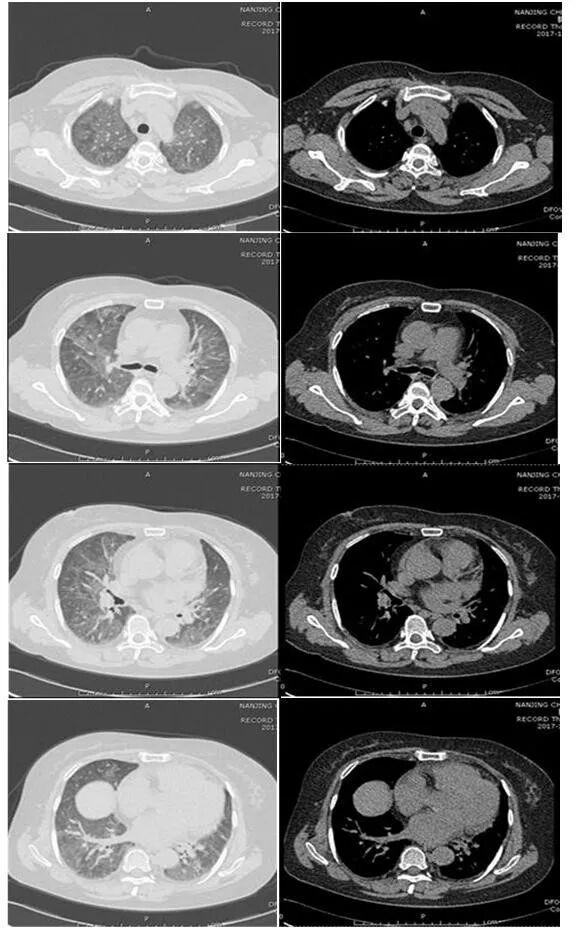

2016年2月患者劳累后再次出现畏寒、发热(体温未测),伴咳嗽、咳痰,门诊查血常规:WBC 14.7×109/L,NEU 88.1%,胸部CT(图1)两肺间质性病变伴感染;心包腔少量积液;两侧胸膜轻度增厚;④左侧乳腺结节影。诊断“肺部感染”,予“美洛西林舒巴坦、喜炎平注射液”治疗后患者无明显改善,渐出现胸闷不适、呼吸困难,查血气:pH 7.477,PaO39.6 mmHg, PaCO36.7 mmHg收住B院。予“哌拉西林他唑巴坦+莫西沙星”治疗3日,症状无好转,更换“亚胺培南西司他丁”抗感染,并予无创机械通气。

图片

图1  胸部CT(2016年2月3日)

注:两肺间质性病变伴感染,心包腔少量积液。两侧胸膜轻度增厚。左侧乳腺结节影

后患者咳嗽、气喘渐好转,复查血常规正常,胸部CT(图2较前有所吸收,2016年2月15日出院。此后患者反复出现上述症状,每年发作2~3次,住院治疗10~15日可缓解。

图2  胸部CT(2016年2月11日

注:两肺间质性改变伴感染,较前部分吸收。心影增大伴心包腔及双侧胸腔少许积液,双侧胸膜轻度增厚